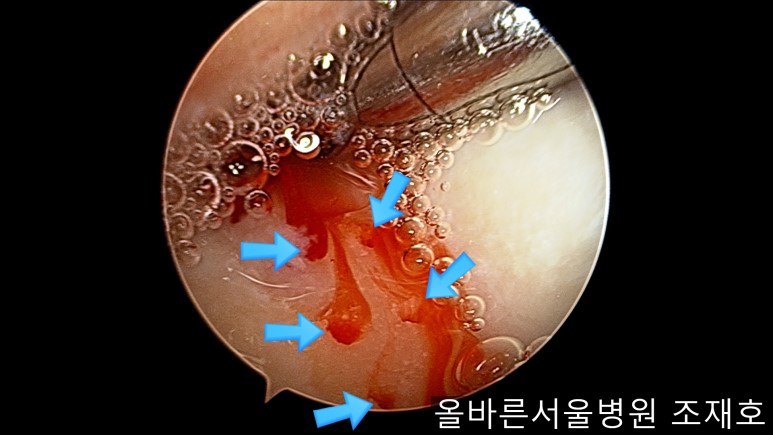

为了软骨再生,在胫骨上端进行微骨折术。

胫骨上端是通过微骨折术,可再生软骨的地方。

尽量将孔打地细密,确认此处骨髓腔内的血流出。

在股骨部位用CARTISTEM注射用4mm激光钻细密打孔,并确保软骨板不倒塌。不用切开通过关节镜即可完成手术。

如图,尽量细密打孔。